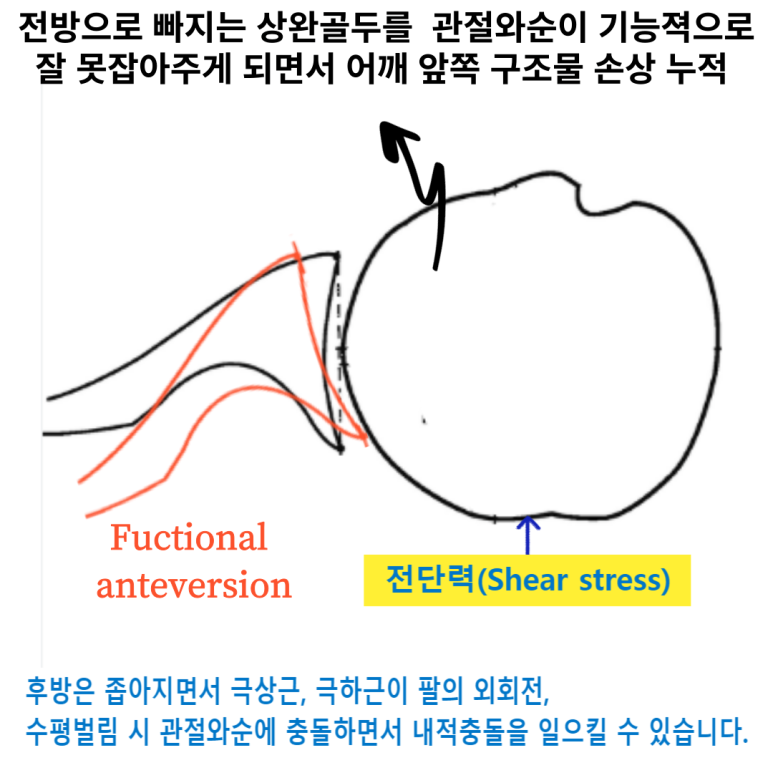

과도한 어깨 앞으로 빠짐상태인 전인 상태가 유지되고, 후인은 잘 되지않게되면 견관절의 관절와(Glenoid)에 해부학적문제가 아닌 기능적인 앞쪽기울어짐(fuctional anteversion)이 발생되면서 관절와순(Glenoid labrum)에 상완골두가 잘 밀착되지 않고 붕 뜨게 되면서 앞쪽 어깨의 안정성이 떨어지면서 손상에 취약하게 됩니다. 이는 결국 어깨 전방 탈구(Anterior dislocation, 어깨 탈구의 95% 차지, https://www.youtube.com/watch?v=xDePRKeB4kc)가 더 쉽게 발생할 수 있게됩니다.

참고로 어깨 앞쪽 전방탈구는 외전, 신전, 외회전 시 발생되며 위와같이 관절와의 기능적인 앞쪽 기울어짐상태 시 더 잘 발생할 수 있습니다.

반면 어깨 뒤쪽은 상대적으로 관절와와 상완골두가 좁아지며 외회전, 수평외전 시 극상근, 극하근이 관절와순과 충돌이 많아지며 내적충돌을 일으킬 수 있습니다.(Internal impingement) 이 때 내적충돌은 전상방, 후상방에서 각각 일어날 수 있고, 주로 후상방에서 나타납니다.